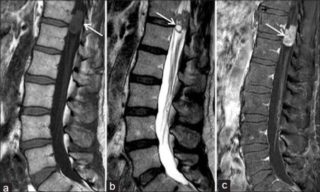

- Гемангиома — это шишка на спине (на позвоночнике), образование которой происходит за счет скопления кровеносных сосудов, которые аномально разрастаются под кожей. Такие уплотнения очень быстро увеличиваются, разрушая при этом окружающие ткани.

Если воспаление под кожей представляет собой гемангиому, то такое образование возникает по причине аномального разрастания кровеносных сосудов, устранить которое не просто. Именно такая припухлось будет отличаться по цвету от других участков кожи.

- гемангиома — патологическое разрастание кровеносных сосудов. Подобные опухоли, хотя и носят доброкачественный характер, развиваются крайне агрессивно, травмируя в процессе роста окружающие ткани;

Гемангиома

Гемангиома — опухоль, состоящая из близко расположенных сосудов

Гемангиома – большое скопление кровеносных сосудов, которое характеризуется быстрым разрастанием за короткий период времени. Носит разрушительный характер, нередко травмирует здоровые сосуды и ткани. Бывает разных размеров, часто болезненна. Отличается ярким цветом. Существующие разновидности: простая, кавернозная, сенильная, комбинированная, капиллярная. Новообразование может перерастать в злокачественную опухоль.